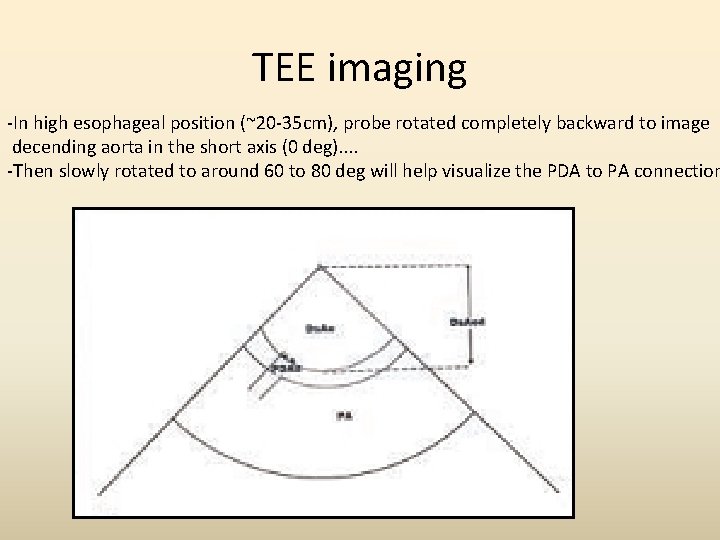

TEE imaging -In high esophageal position (~20 -35 cm), probe rotated completely backward to image decending aorta in the short axis (0 deg). . -Then slowly rotated to around 60 to 80 deg will help visualize the PDA to PA connection